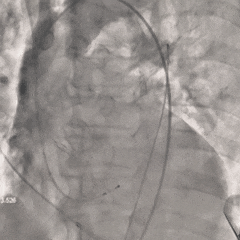

最终评估

超声测量AVmax=2.1m/s,PGmax=17mmHg,提示少量瓣周漏,间隔侧瓣架深度为真实瓣环零位

考虑球囊后扩的操作会进一步增加冠脉阻挡风险,并存在较高瓣膜上跳风险,综合患者情况可,决定不再进行球囊后扩。

术后超声

-

峰值流速:4.9m/s(术前)→2.0m/s(术后)

峰值压差:95mmHg(术前)→15mmHg(术后)

瓣口未见明显反流,瓣周轻度反流,手术顺利完成!